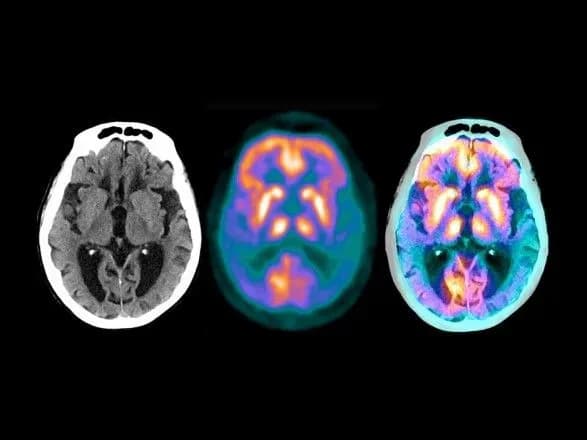

Вчені вважають, що головна причина цього захворювання полягає в тому, що в мозку накопичується патогенний білок — бета-амілоїд. Він являє собою уривки білка APP, який грає важливу роль у формуванні зв’язків між нейронами. За поки невідомих причин процес переробки цього білка порушується.

Донанемаб, який розробляють фахівці Eli Lilly, націлений на одну з форм бета-амілоїду — N3pG. Друга фаза клінічних досліджень, в якій брали участь 272 пацієнта з хворобою Альцгеймера різної тяжкості, показала, що після прийому цього препарату у 32% пацієнтів хвороба прогресувала набагато повільніше, ніж у тих людей, хто замість ліків приймав плацебо.